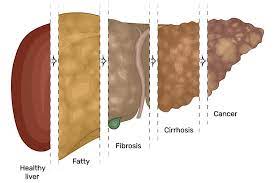

قیمت: 32٬000 تومان - دسته بندی فایل: پاورپوینتپاورپوینت تغییر چربی کبد

فروش ویژه پاورپوینت حرفه ای تغییر چربی کبد با تخفیف استثنایی فقط 62 هزار تومان تعداد اسلاید: 26 اسلاید